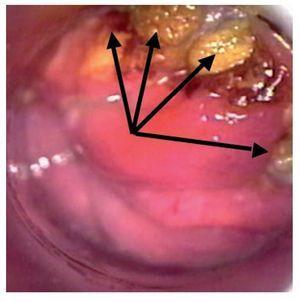

La anoscopia de alta resolución se realizó mediante la siguiente técnica: previa firma del consentimiento informado y con paciente en posición proctológica, se realizó tacto rectal para dilatación del ano, se introdujo anoscopio y se revisó el conducto anal en búsqueda de lesiones macroscópicas. Se aplicó ácido acético a 3% con un hisopo y se retiró el anoscopio. El hisopo se dejó en contacto con las paredes el conducto anal por un minuto y se retiró. Se introdujo nuevamente el anoscopio y se realizó la observación del conducto anal con microscopio de alta resolución. En los casos que se consideró necesario, a criterio del colposcopista, se utilizó la prueba de Schiling para detectar las lesiones sospechosas. Esta prueba consiste en aplicar una solución yodoyodurada de lugol a 1% o 2%, con el objeto de obtener imágenes yodo negativas (que no fijan el lugol), yodo positivas o yodo débiles (que fijan el lugol). El fundamento es que únicamente los tejidos maduros, provistos de glucógeno fijan el yodo, razón por la que el epitelio maligno o atípico es yodo negativo (Figuras 1-3). En las lesiones que resultaron dudosas para VPH o NIA se tomaron 1 o 2 biopsias de la lesión sospechosa. Previo al procedimiento, los pacientes acudieron con preparación intestinal a base de enemas de fosfato. No se administró profilaxis antibiótica y el procedimiento se realizó sin anestesia.

Figura 2. Anoscopia de alta resolución muestra un patrón aceto-blanca difuso con puntilleo vascular y ulceración. Lesión sospechosa de neoplasia intraepitelial anal de bajo grado, en la cual se utilizó filtro para resaltar la lesión